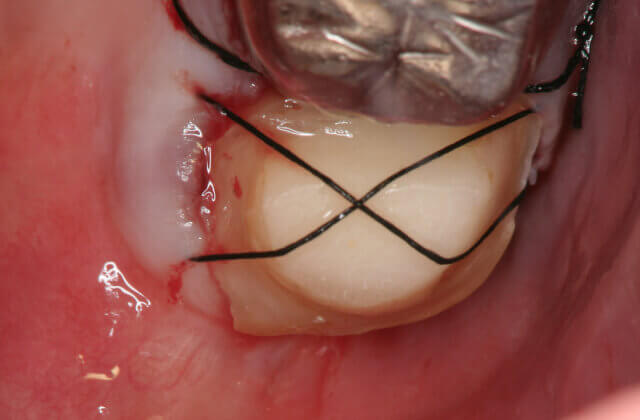

被せ物をした歯の違和感により来院されました